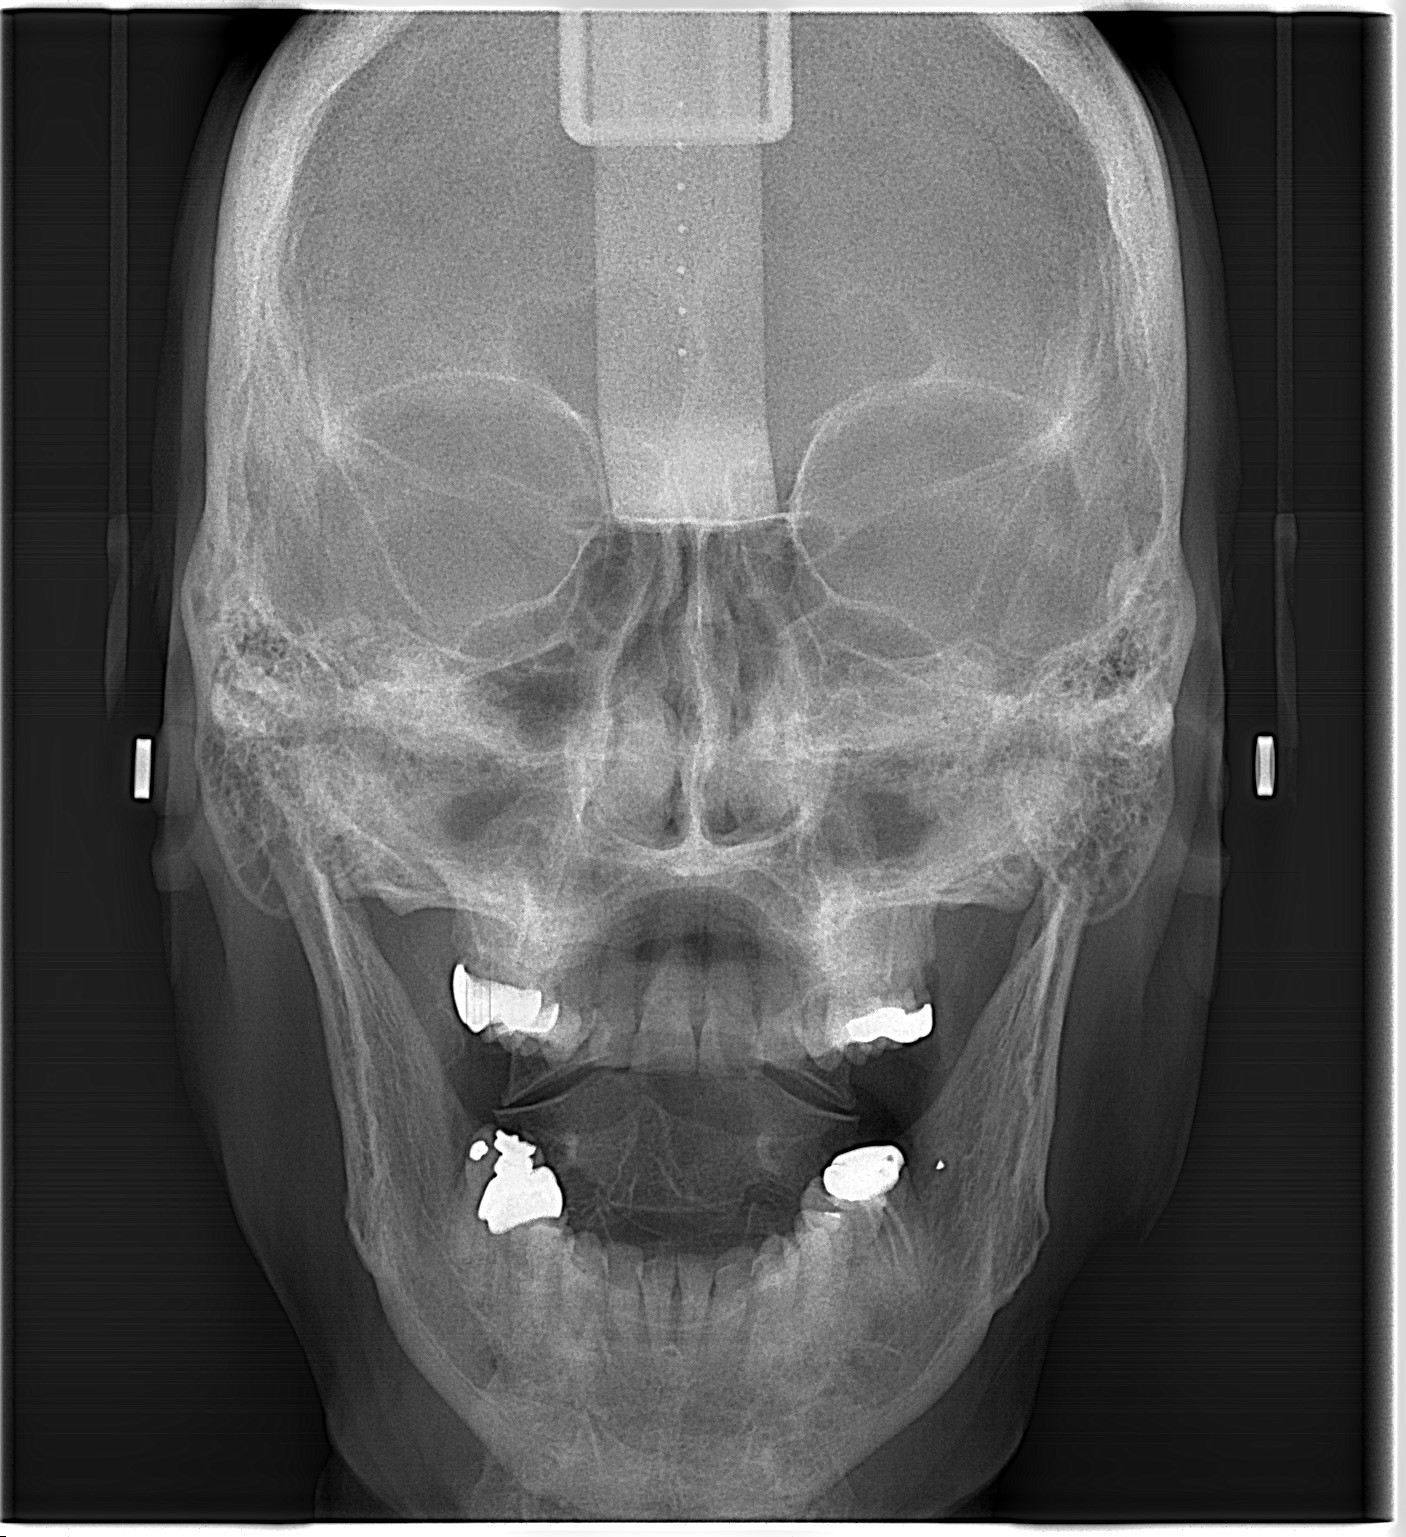

- Radiografía AP y PA: Radiografía utilizada para evaluar principalmente asimetrías faciales, seno frontal y etmoidal, fosas nasales y orbitas.

La radiografía panorámica ofrece una vista general del paciente, permitiendo evaluar dientes, hueso alveolar, maxilares y estructuras adyacentes para un diagnóstico integral.